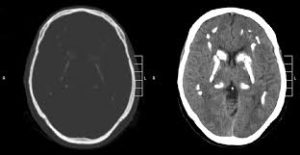

neurologies https://www.neurologies.net santé & bien être mental avec neurologies.net Fri, 07 Jun 2024 19:30:58 +0000 fr-FR hourly 1 https://wordpress.org/?v=6.5.4 https://www.neurologies.net/wp-content/uploads/2021/01/cropped-icone-1-32x32.png neurologies https://www.neurologies.net 32 32 Le syndrome de Fahr, comment ça se présente ? https://www.neurologies.net/le-syndrome-de-fahr-comment-ca-se-presente/ https://www.neurologies.net/le-syndrome-de-fahr-comment-ca-se-presente/#respond Fri, 07 Jun 2024 19:26:08 +0000 https://www.neurologies.net/?p=211 Le patient est confirmé d’avoir le syndrome de Fahr en cas d’association d’une symptomatologie typique et d’images caractéristiques au scanner cérébral ou l’IRM. Il n’y a aucun traitement spécifique pour ce syndrome.

Le syndrome de Fahr est une affection neurologique qui inclut les troubles psychiatriques et cognitifs, des impulsions inhabituelles et des calcifications caractéristiques visibles sur l’imagerie cérébrale. Elle est une cellule anatomoclinique rare qui se situe dans les noyaux gris centraux.

La plupart du temps, le syndrome de Fahr touche les personnes âgées de 40 à 50 ans avec une supériorité masculine. Il est causé par les dépôts de calcium et d’autres minéraux dans les parois vasculaires, mais également dans les espaces péri-vasculaires du cerveau, particulièrement dans les noyaux gris centraux.Ces dépôts peuvent être à l’origine du désordre même si les processus ne sont pas déterminés. Le syndrome de Fahr peut être familial ou individuel. S’il est familial, il y a une transmission génétique.